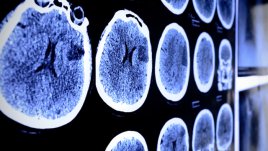

Качеството на живот на жените, преживели мозъчен удар, е значително по-лошо в сравнение с мъже със сходна диагноза